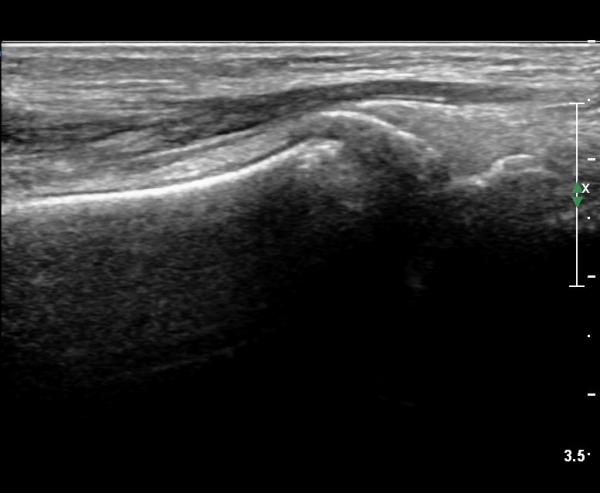

she revealed limping gait. on examination, there is swelling around ankle with limited ankle motion, localized tenderness at distal tibiofibular ligament and ATF ligament.

ÃÊÀ½ÆÄ °Ë»ç